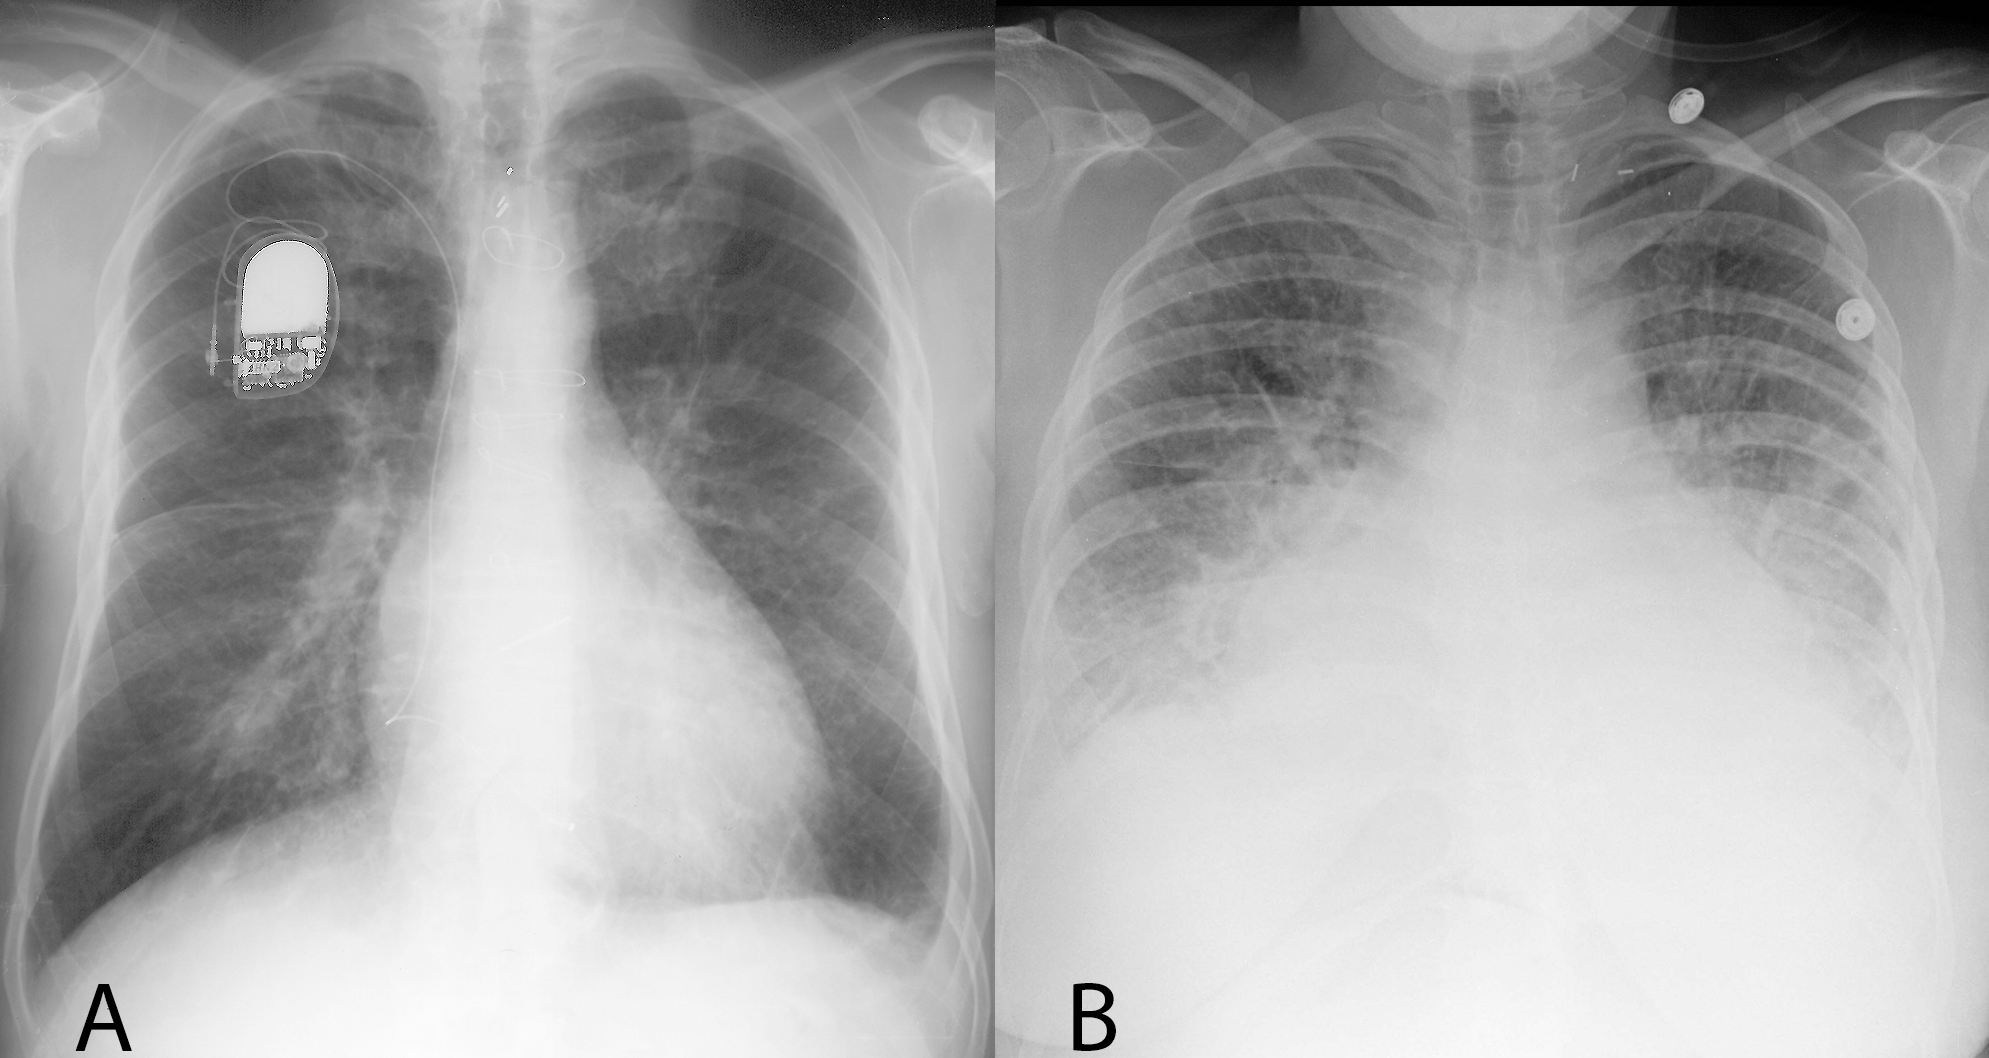

Third pair--both patients have lung opacities, but one is a simple pneumonia while the other has evidence of adenopathy and cavitation, suggesting a more complicated process.